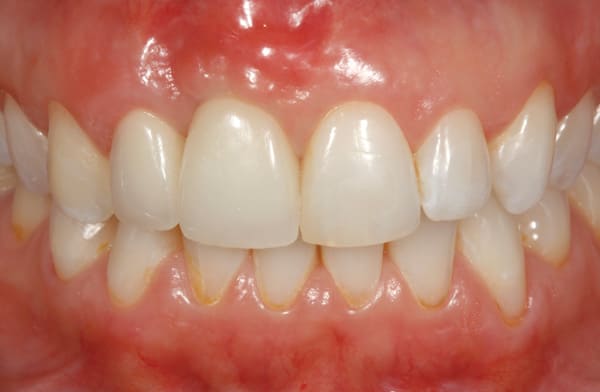

After 6 months of healing of the implant, stage 2 uncovering was performed and the mucosal tissues were allowed to mature for another 2 to 3 weeks. A temporary screw-retained implant cylinder (PreFormance® Temporary Cylinder, Biomet 3i) was joined to the implant and acrylic (Super-T, American Consolidated Mfg, www.pattersondental.com) crown (Figure 8). The subgingival shape of the temporary was modified with additional acrylic and the technique of non-surgical tissue sculpting, which was developed to provide the proper emergence profile to the mucosal tissues.27 It is important that the temporary blanching (ischemia) of the mucosal tissues dissipate after 10 minutes (Figure 9). After 3 weeks, soft-tissue scalloping through gingivectomy was done to recreate the proper shape (ie, gingival zenith)28 and proportion for the mucosal tissues (Figure 10). Fiberotomy on the distal aspect of tooth No. 7 was not performed during treatment; therefore, this papilla was slightly more incisal (longer) than the adjacent papillae (Figure 11). A final impression was made of crown No. 7 and implant No. 8 at the implant level to enable a working cast to be made in the laboratory. An all-ceramic custom abutment was made for implant No. 8 (BellaTek® Encode, Biomet 3i), and splinted full-coverage units were made for crowns No. 7 and No. 829 (Figure 12). The custom abutment was seated intraorally and torqued according to the manufacturer’s recommendation. The crowns were luted with provisional cement (Tempbond® NE, Kerr Dental, www.kerrdental.com) and maintained at 4-month recall intervals (Figure 13). Note the health of the periodontal tissues and their integration with the adjacent teeth and surrounding gingiva, taking a complex esthetic and functional problem for a patient with a high smile line and providing a predictable restorative and esthetic outcome (Figure 14).